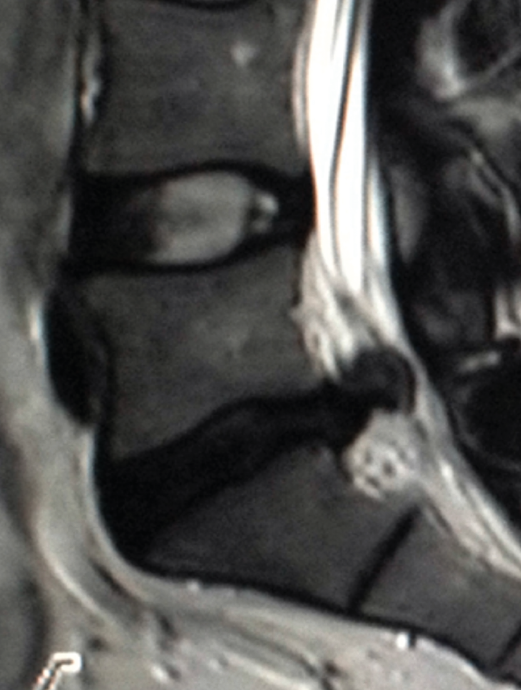

Ofrece una excelente definición de las estructuras blandas (tanto intra- como extrarraquídeas). Permite una buena visualización del saco dural y su contenido, sin la necesidad de tener que inyectar contraste intratecal, además de permitir la detección de patologías intramedulares. Es, por tanto, la técnica diagnóstica de elección ante la sospecha de una patología específica de partes blandas, discos intervertebrales, ligamentos y saco neural, así como en la evaluación de una posible afectación tumoral, infecciosa o metabólica del raquis vertebral lumbar (Figura 13).

Las principales indicaciones para el empleo de esta técnica en el estudio de la patología dolorosa lumbar serían:

- La sospecha clínica de hernia discal: de elección, especialmente en pacientes jóvenes sin signos de espondilosis ni estenosis del canal vertebral; debería reservarse para pacientes candidatos a un tratamiento quirúrgico o aquellos que, con síntomas o signos de radiculopatía, no responden adecuadamente al tratamiento conservador pautado durante un periodo variable de 4 a 6 semanas.

- La valoración del dolor lumbar tras una cirugía vertebral discal: constituye el único método diagnóstico para diferenciar una cicatriz fibrosa por una probable fibrosis posquirúrgica de una recidiva herniaria, con una precisión cercana al 98%.